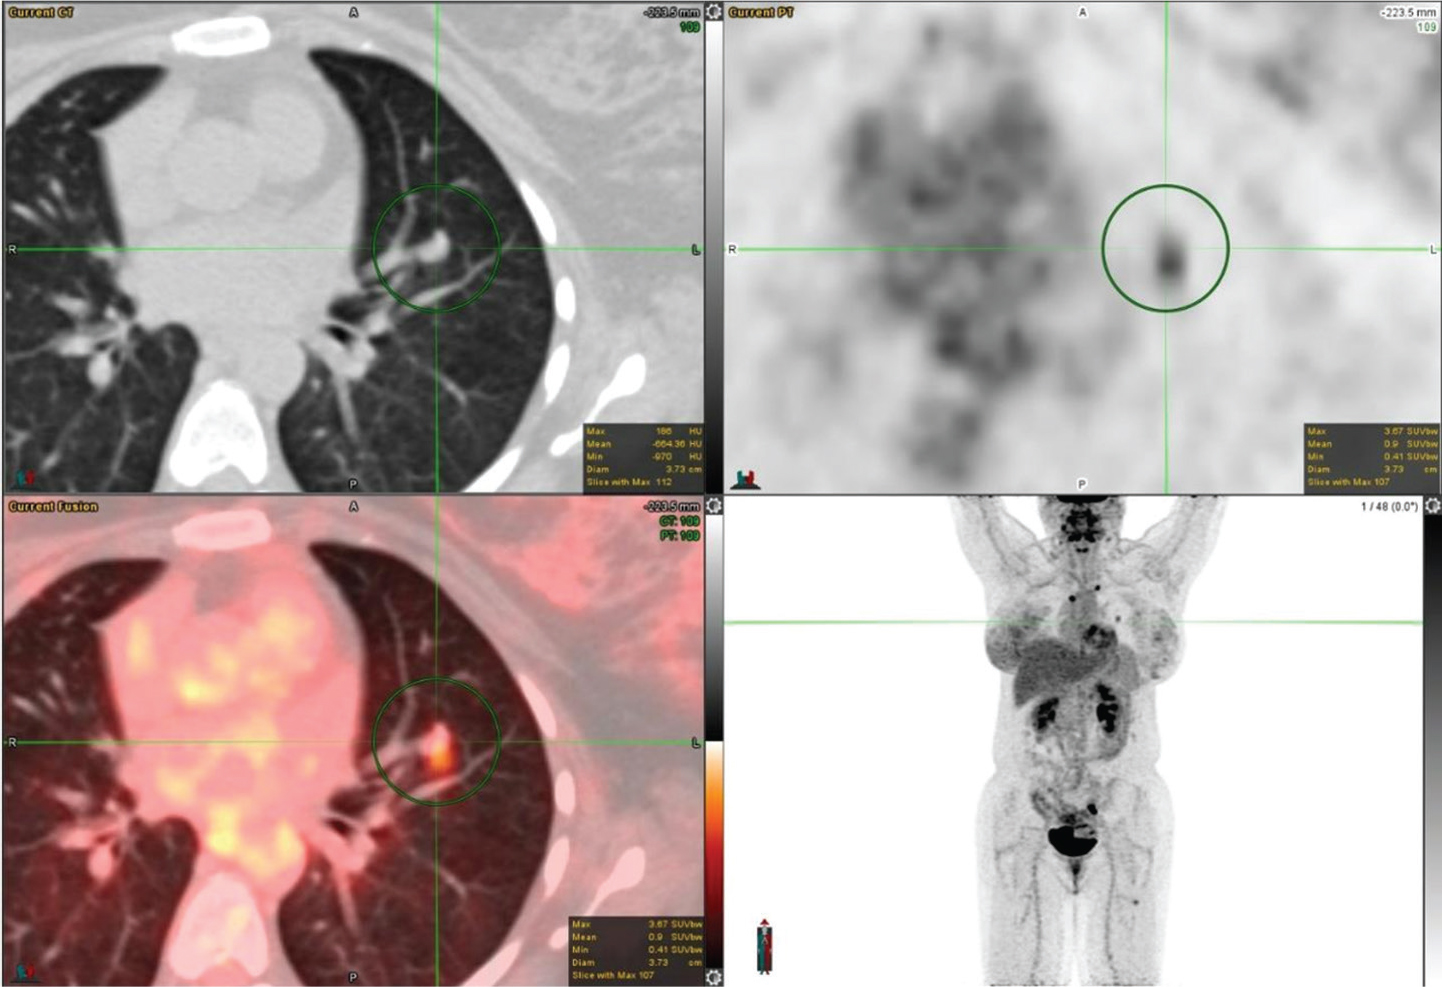

The FDG avidity of lung cancer is mainly dependent on two factors: tumor size, and histology. For nodules greater than 8 mm, 18F-FDG PET/CT has a high negative predictive value in excluding malignancy (20). Squamous cell carcinoma tends to have a higher uptake as shown in Figure 3. Low-grade adenocarcinoma, mucinous adenocarcinoma, colloid carcinoma, and typical carcinoid can have very low FDG avidity. Bronchoalveolar carcinoma (BAC), a well-differentiated subtype tends to have peak SUV (1.5 ± 0.2) lower than all other non-BAC adenocarcinomas (SUV, 3 ±1.5). False positive FDG uptake can be seen in infectious and inflammatory lesions.

Fig 3

Figure 3. Right upper lung mass that was pathologically confirmed as squamous cell carcinoma. FDG PET/CT images include axial CT (top left panel), axial PET (top right panel), fused axial PET/CT (bottom left panel), and maximum intensity projection (MIP) PET image (bottom right panel). In the green circle, there is a lobulated and spiculated right upper lobe mass on CT with intense FDG uptake on PET.